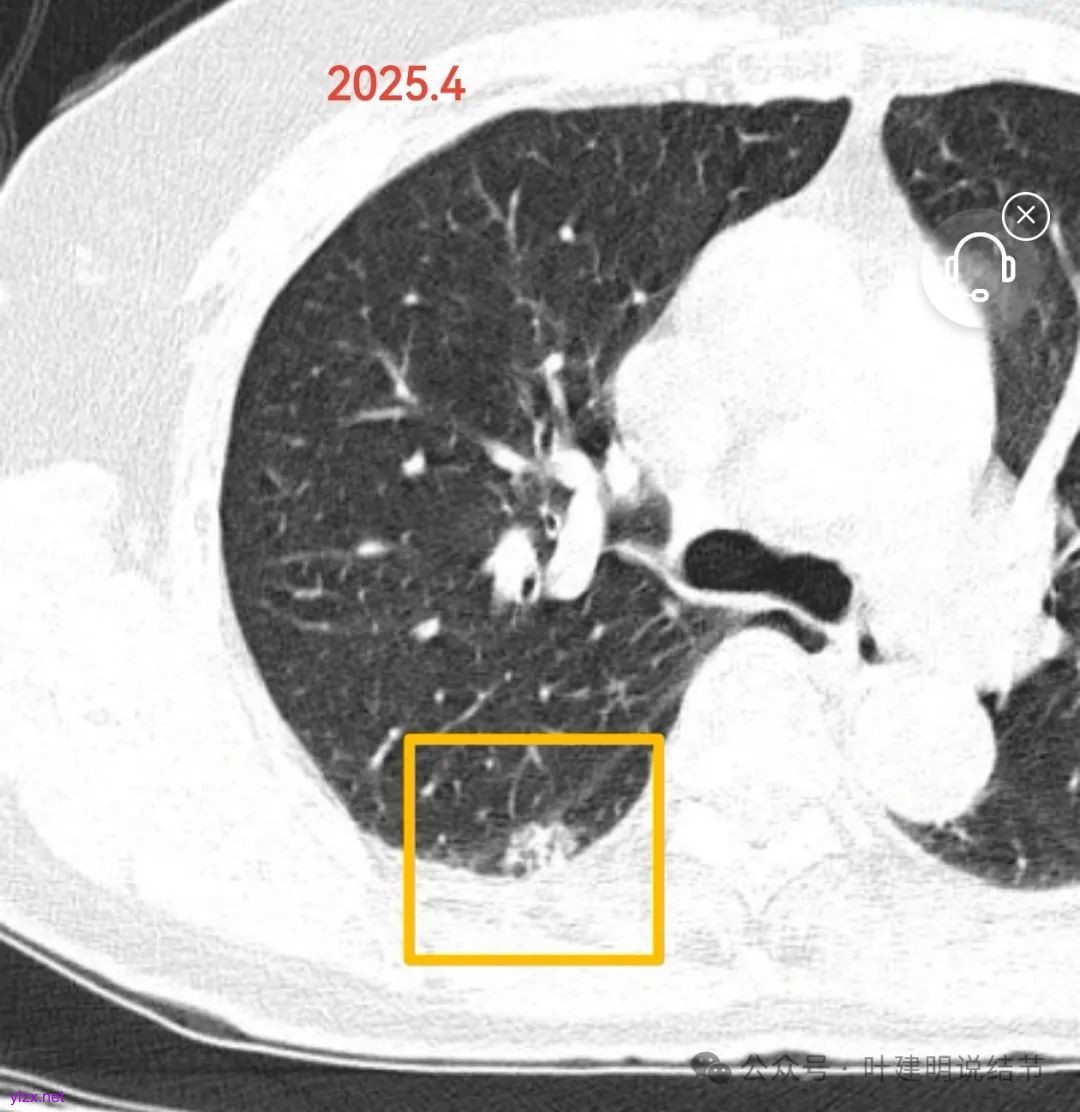

右肺下叶背段这个病灶,对比两次的CT,感觉密度略有减低,整体轮廓显得稍微清楚点起来。至少没有进展,这种似乎有点改变比较符合炎症性的变化。如果单看复查这次的,只从影像考虑更符合恶性一些。对比看就不是太符合。我稍微倾向于再过3~4个月再复查一次再看情况。当然已经随访过,如果比较担心,由于病灶位置非常好,单孔胸腔镜下局部切除很方便,即使去除病灶也是明确诊断,考虑近期切了也是可行的。但是要有切了以后是良性的思想准备。意见供参考!

这个病灶感觉对比是略有变散,病灶内部有了一些小的空腔,为什么结果仍然是恶性而且是浸润性粘液腺癌?再回过去分析,我想我们仍然要抓住肺结节轮廓整体上较为清楚这个特征。只要随访过,整体轮廓清楚,就得提高警惕。对于这种位置比较靠边缘部位的,密度不纯的,可能还是要更加积极一点手术干预。当然,倒不是说这个病例如果在随访3~4个月或者4~6个月,影像上面有所进展或者没有好转再开就会转移或者影响预后,那样应该也是可以的。两次的形态和密度略有不同,可能与扫描条件不一样有一定的关系。